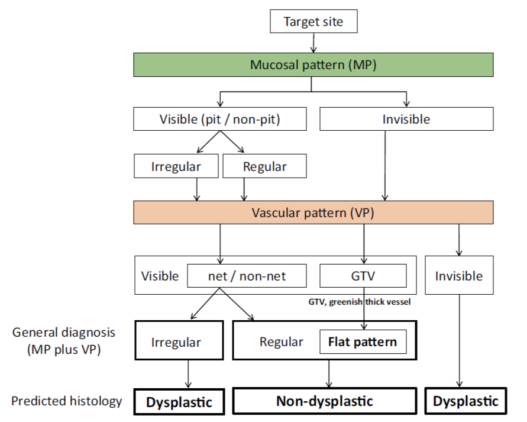

According to the morphology of the anatomical components, the MV and MS patterns were classified as regular, irregular, or absent (. Fig. 2). In principle, the MV and MS patterns must be determined separately.

DL is defined as the border between the lesion and non-lesion areas, discernible through an abrupt change in MV and/or MS patterns (. Fig. 2).

The criteria for high-grade dysplasia (HGD)/early cancer (EC) are as follows:

- Presence of an irregular MV pattern with a demarcation line.

- Presence of an irregular MS pattern with a demarcation line.

A target lesion is diagnosed as HGD/EC if it fulfills both or either of the criteria. If it does not meet either of the criteria, it is diagnosed as noncancerous.

The working group members carried out a systematic review of the English literature to determine widely accepted diagnostic systems. Consequently, the best-accepted diagnostic system was proven to be the VS classification system. Based on this system, MESDA-G was constructed using an evidence-based approach (. Figs. 3, 4, 5, and 6) [2]. First, lesions suspicious for EGC should be detected by careful inspection using conventional white-light endoscopy. Subsequently, magnified observations should be performed. Owing to the high sensitivity of the demarcation line [8], if it is absent, the suspicious lesion is diagnosed as noncancerous (. Fig. 4a, b). However, if the demarcation line is present, further assessment is required to determine the presence of an irregular MV or MS pattern. If an irregular MV and/or MS pattern is detected, the suspicious lesion is diagnosed as cancerous (. Fig. 6a, b) [1, 5, 6, 8]. If both the irregular MV and MS patterns are absent, the tumor is diagnosed as noncancerous (. Fig. 5a, b) [1, 5, 6, 8].